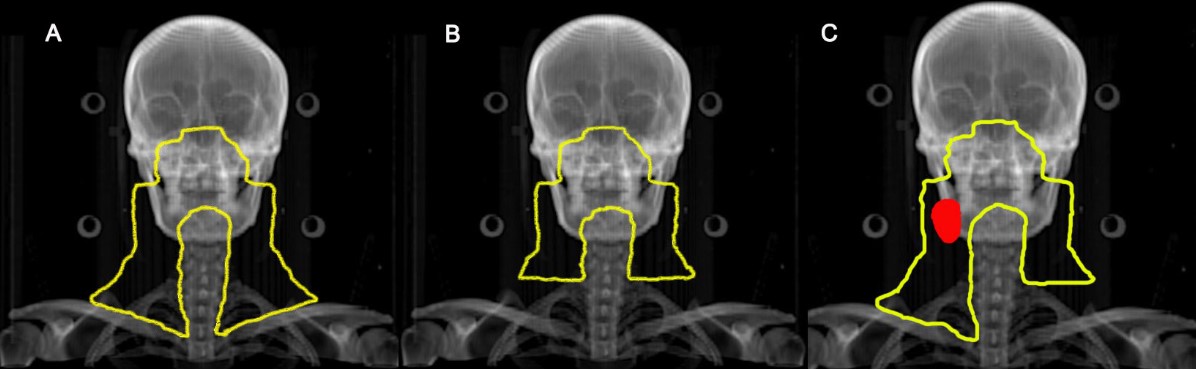

鼻咽癌预防照射范围示意图

A:对照组:无论有无淋巴结转移均行全颈部预防照射

B:试验组:无颈部淋巴结转移,双侧颈部行上半颈部照射

C:试验组:单侧淋巴结转移(红色区域),淋巴结阴性侧行上半颈部照射